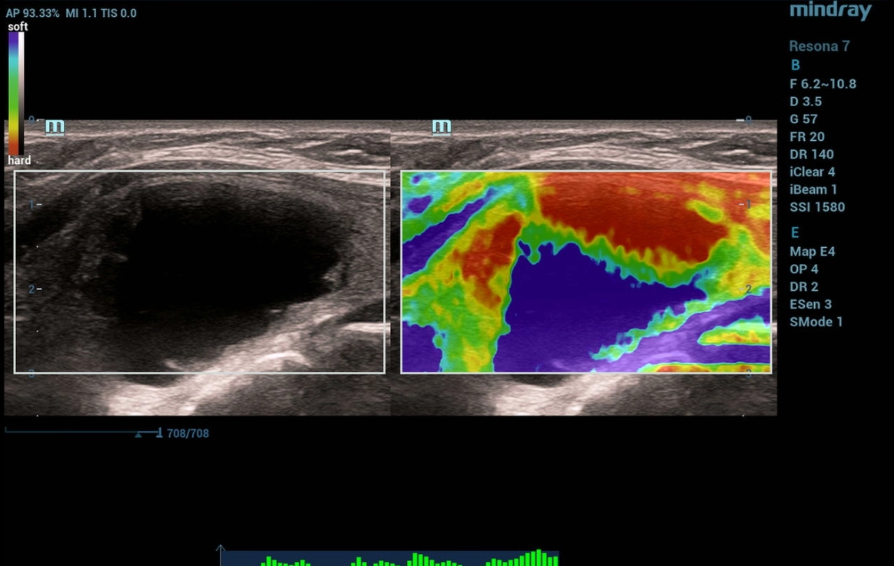

Ultrasonography was performed on a Resona 7 ultrasound machine (Mindray, China) using a linear probe L14-5WU. A cystic focal mass of anechogenic structure measuring 24x28x38 mm with smooth clear contours was detected in the left lobe of the thyroid gland (Fig. 1, 2)

In Color Flow Doppler (CFD) there is no blood flow in the focal mass with the presence of single perinodular vessels (Fig.2)

Strain elastography identifies a tricolor structure (BGR sign - blue/green/red layers) of the focal mass, which is consistent with cystic contents (Figure 3).

Multiparametric ultrasound examination of the thyroid revealed a cystic focal mass in the left lobe without signs of malignancy.

On strain elastography, the focus had tricolor staining (BGR sign) consistent with a cystic mass.